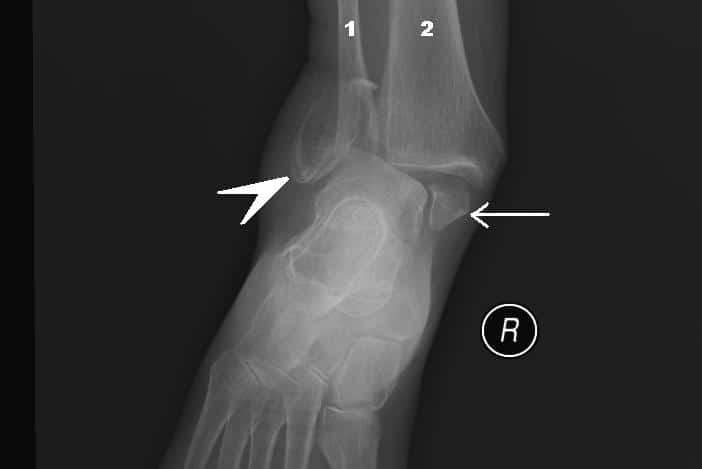

The ankle joint (or talocrural joint) is a synovial joint located in the lower limb. It is formed by the bones of the leg (tibia and fibula) and the foot (talus). Functionally, it is a hinge type joint, permitting dorsiflexion and plantarflexion of the foot. In this article, we shall look at the anatomy of the ankle joint; its articulating surfaces, ligaments, movements, and clinical correlations. By TeachMeSeries Ltd (2025) Fig 1The bones of the ankle joint; tibia, fibula and talus. Note that the calcaneous is not considered part of the ankle joint. Pro Feature - 3D Model You've Discovered a Pro Feature Access our 3D Model Library Explore, cut, dissect, annotate and manipulate our 3D models to visualise anatomy in a dynamic, interactive way. Learn More Articulating Surfaces The ankle joint is formed by three bones; the tibia and fibula of the leg, and the talus of the foot: The tibia and fibula are bound together by strong tibiofibular ligaments. Together, they form a bracket shaped socket, covered in hyaline cartilage. This socket is known as a mortise. The body of the talus fits snugly into the mortise formed by the bones of the leg. The articulating part of the talus is wedge shaped – it is broad anteriorly, and narrow posteriorly: Dorsiflexion – the anterior part of the talus is held in the mortise, and the joint is more stable. Plantarflexion – the posterior part of the talus is held in the mortise, and the joint is less stable. By TeachMeSeries Ltd (2025) Fig 2X-ray of a normal ankle joint. Note the bracket shaped socket formed by the tibia and fibula. By TeachMeSeries Ltd (2025) Fig 3The talus. It is broad anteriorly, which strengthens the joint during dorsiflexion. Ligaments There are two main sets of ligaments, which originate from each malleolus. Medial Ligament The medial ligament (or deltoid ligament) is attached to the medial malleolus (a bony prominence projecting from the medial aspect of the distal tibia). It consists of four ligaments, which fan out from the malleolus, attaching to the talus, calcaneus and navicular bones. The primary action of the medial ligament is to resist over-eversion of the foot. Lateral Ligament The lateral ligament originates from the lateral malleolus (a bony prominence projecting from the lateral aspect of the distal fibula). It resists over-inversion of the foot, and is comprised of three distinct and separate ligaments: Anterior talofibular – spans between the lateral malleolus and lateral aspect of the talus. Posterior talofibular – spans between the lateral malleolus and the posterior aspect of the talus. Calcaneofibular – spans between the lateral malleolus and the calcaneus. By OpenStax College [CC BY 3.0], via Wikimedia Commons Fig 4Ligaments of the ankle joint. Clinical Relevance The Ankle ‘Ring’ The ankle joint and associated ligaments can be visualised as a ring in the coronal plane: The upper part of the ring is formed by the articular surfaces of the tibia and fibula. The lower part of the ring is formed by the subtalar joint (between the talus and the calcaneus). The sides of the ring are formed by the medial and lateral ligaments. A ring, when broken, usually breaks in two places (the best way of illustrating this is with a polo mint – it is very difficult to break one side without breaking the other). When dealing with an injury to the ankle joint, a clinician must bear this in mind. For example, a fracture of the ankle joint may occur in association with ligament damage (which would not be apparent on x-ray). Movements and Muscles Involved The ankle joint is a hinge type joint, with movement permitted in one plane. Thus, plantarflexion and dorsiflexion are the main movements that occur at the ankle joint. Eversion and inversion are produced at the other joints of the foot, such as the subtalar joint. Plantarflexion – produced by the muscles in the posterior compartment of the leg (gastrocnemius, soleus, plantaris and posterior tibialis). Dorsiflexion – produced by the muscles in the anterior compartment of the leg (tibialis anterior, extensor hallucis longus and extensor digitorum longus). Neurovascular Supply The arterial supply to the ankle joint is derived from the malleolar branches of the anterior tibial, posterior tibial and fibular arteries. Innervation is provided by tibial, superficial fibular and deep fibular nerves. Clinical Relevance Ankle Sprain An ankle sprain refers to partial or complete tears in the ligaments of the ankle joint. It usually occurs via excessive inversion to a plantarflexed and weight-bearing foot. The lateral ligament is more likely to be damaged for two main reasons: The lateral ligament is weaker than the medial ligament. The lateral ligament resists inversion. The anterior talofibular ligament is the lateral ligament most at risk of irreversible damage. Clinical Relevance Pott’s Fracture-Dislocation A Pott’s fracture is a term used to describe a bimalleolar (medial and lateral malleoli) or trimalleolar (medial and lateral malleoli, and distal tibia) fracture. This type of injury is produced by forced eversion of the foot. It occurs in a series of stages: Forced eversion pulls on the medial ligaments, producing an avulsion fracture of the medial malleolus. The talus moves laterally, breaking off the lateral malleolus. The tibia is then forced anteriorly, shearing off the distal and posterior part against the talus. By Steven Fruitsmaak [CC BY-SA 3.0], from Wikimedia Commons Fig 5Bimalleolar fracture of the ankle. 1 – Fibula, 2 – Tibia. Do you think you’re ready? Take the quiz below Pro Feature - Quiz The Ankle Joint Question 1 of 3 Submitting... Skip Next Rate question: You scored 0% Skipped: 0/3 1800 More Questions Available Upgrade to TeachMeAnatomy Pro Challenge yourself with over 1800 multiple-choice questions to reinforce learning Learn More Rate This Article